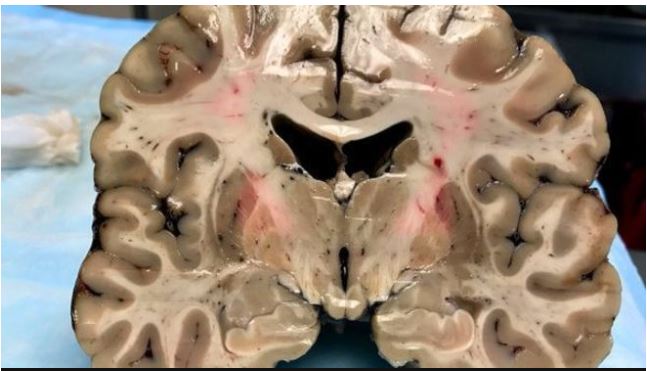

Colocado sobre una mesa de laboratorio, horas después de su muerte, el cerebro de Aaron Hernández ofrecía una apariencia saludable.

A pesar de su apariencia saludable exterior, el cerebro de Hernández estaba profundamente dañado por la encefalopatía traumática crónica. (Foto Prensa Libre: cortesía Boston University)

Pero lo que en principio parecía un cerebro sano, escondía debajo de su superficie un secreto que sorprendió a los científicos que llevaron a cabo la autopsia del jugador.

El órgano mostró un estado de encefalopatía traumática crónica (CTE, por sus siglas en inglés) similar al de alguien afectado por esa enfermedad cerebral degenerativa de 60 años.

Los científicos estadounidenses lo consideran el caso más grave jamás registrado en alguien de su edad.

Al cortarlo en pedazos de 1.3 centímetros, los investigadores notaron la existencia de “cuevas” de un tamaño inusual en el centro del órgano, que se expandían a medida que el tejido cerebral disminuía.

Según Caramelli, se trata de algo poco común para una persona de 27 años, edad en la que el cerebro suele ocupar casi todo el cráneo.

El equipo de McKee también observó que el septo pelúcido, una membrana que divide los dos lados del cerebro, estaba perforada, situación que suele ocurrir con los pacientes que padecen CTE.

No obstante, el principal indicio de esa enfermedad se encontró cuando colocaron el cerebro de Hernández debajo del microscopio y se percataron de una acumulación excesiva de proteína tau, que mata las células nerviosas.